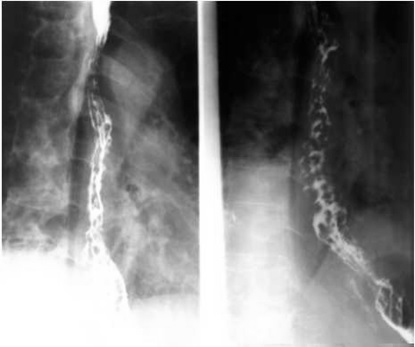

05卷-5.男性,胸骨后隱痛一年,請選擇正確答案(本題滿分2.00分)

本題答案:B

題目解析:【該題針對“造影-食管靜脈曲張”知識點進(jìn)行考核】